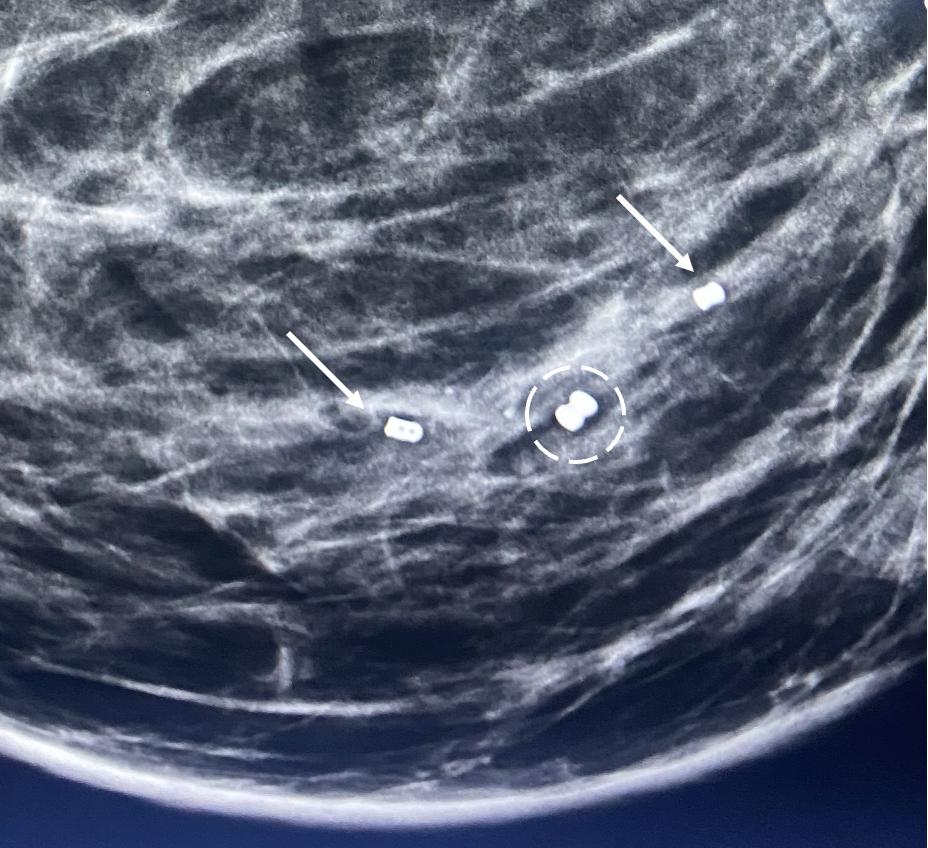

Placement of biopsy site marker(s). Regardless of cancer size, insertion of a biopsy site marker (also called a “clip” or “chip”) at the time of mammogram-, ultrasound-, or MRIguided needle biopsy is recommended to document the site of the cancer. In situations where pre-cryoablation chemotherapy and/or anti-HER2/neu therapy is planned, insertion of a biopsy site marker prior to initiation of anticancer medications documents the location of the cancer in the event drug therapy-induced shrinkage of the cancer makes it difficult to detect by ultrasound (Image 5).

Image 5. Mammogram performed before (A) pre-operative chemotherapy showing large, white, ultrasound visible cancer encircled by hash marks. After completing pre-operative chemotherapy, a repeat mammogram (B) of the same breast showed complete disappearance of the original cancer leaving only a circular metal biopsy site marker (arrow) to indicate the location of the original cancer.

Biopsy site markers come in many shapes and sizes, but most measure less than 10 mm length. In breast radiology, the most commonly used biopsy site markers are metallic (stainless steel, titanium, or nickel) devices that are optimized for detected by mammography, but poorly visible by ultrasound. However, several biopsy site markers have been optimized for ultrasound detection by encasement of the metallic component in a larger, absorbable collagen or hydrogel sleeve (Image 6). For cancer that are already visible by ultrasound, the type of marker is unimportant as the tumor itself provides an obvious target for ultrasound-guided cryoablation. However, when the breast cancer is very small or invisible to ultrasound, insertion of an ultrasound-visible marker at the time of the initial needle biopsy or subsequently will facilitate ultrasound-guided cryoablation of the ultrasound-occult cancer.

Generally, a single biopsy site marker is sufficient for marking the site of most breast cancers.

However, patients with a wide span of disease may benefit from placement of two or more ultrasound-visible markers to outline or bracket the borders of the cancer to improve targeting of the cryoablation treatment (Image 7).

Image 6. Ultrasound image (A) showing an example of a 2 cm long, basket-like, tubular, ultrasound-visible biopsy site marker (bracketed by paired arrows) that documents the location of ductal carcinoma in situ, which itself was not ultrasound visible. Image B shows enlarged view of actual basket-like marker and the shapes of various radio-opaque markers they may contain.

Image 7. Mammogram showing the metal components (indicated arrows) of two ultrasound-visible biopsy site markers on opposite sides of the original metal biopsy site marker (encircled by hash marks) that was placed at the time of the diagnostic needle biopsy. The original biopsy site marker was not ultrasound visible.